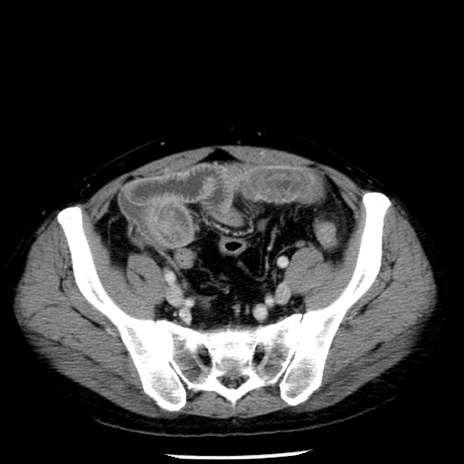

症例29(横断像)

【症例】40歳代男性

【現病歴】2日前から胃痛あり。徐々に周期的な激痛に変化した。本日になっても激痛があるため受診。

【身体所見】意識清明、BT 38-39℃台あり、腹部:膨満、やや硬、右下腹部に圧痛あり。

【データ】WBC 8500、CRP 23.26